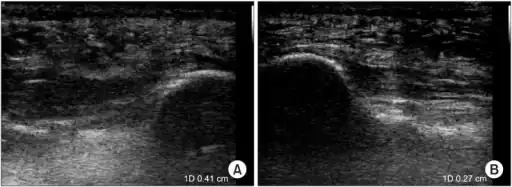

a)Ultrasonographic finding of plantar fasciitis b)normal sonographic finding -

Thickened plantar fascia in ultrasound

The plantar fascia has three fascicles-the central fascicle being the thickest at 4 mm, the lateral fascicle at 2 mm, and the medial less than a millimeter thick.[18] In theory, plantar fasciitis becomes more likely as the plantar fascia's thickness at the calcaneal insertion increases. A thickness of more than 4.5 mm ultrasound and 4 mm on MRI are useful for diagnosis.[19] Other imaging findings, such as thickening of the plantar aponeurosis, are nonspecific and have limited usefulness in diagnosing plantar fasciitis.[13]